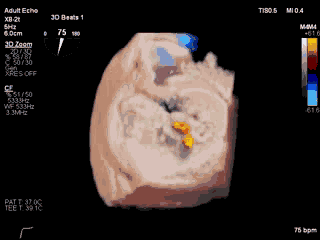

视频6 经食道三维超声心动图显示在植入第二枚MitraClip NTR夹合器后,二尖瓣呈双孔启闭,两枚夹合器位置、结构正常

4月11日上午患者在全麻下接受MitraClip经皮二尖瓣夹合术。术中穿刺右股静脉,经食道超声心动图(TEE)再次评估瓣膜病变(视频1),并引导顺利穿刺房间隔(视频2)。随后送入二尖瓣夹合系统,在TEE引导下于二尖瓣P2区植入MitraClip XTR夹合器一枚(视频3),二尖瓣关闭不全减轻,但夹合器内侧仍存在反流(视频4)。团队决定为患者植入第二枚夹合器(MitraClip NTR),手术过程顺利(视频5)。TEE三维显示在植入第二枚NTR夹合器后,二尖瓣呈双孔启闭,两枚夹合器位置、结构正常(视频6)。配备心腔镜功能的TEE三维TrueVue彩色多普勒显示二尖瓣反流将至少量(视频7),且未致二尖瓣口狭窄(图1),夹合效果满意。手术通过视频连线得到香港亚洲心脏病中心主任林逸贤教授的技术支持。